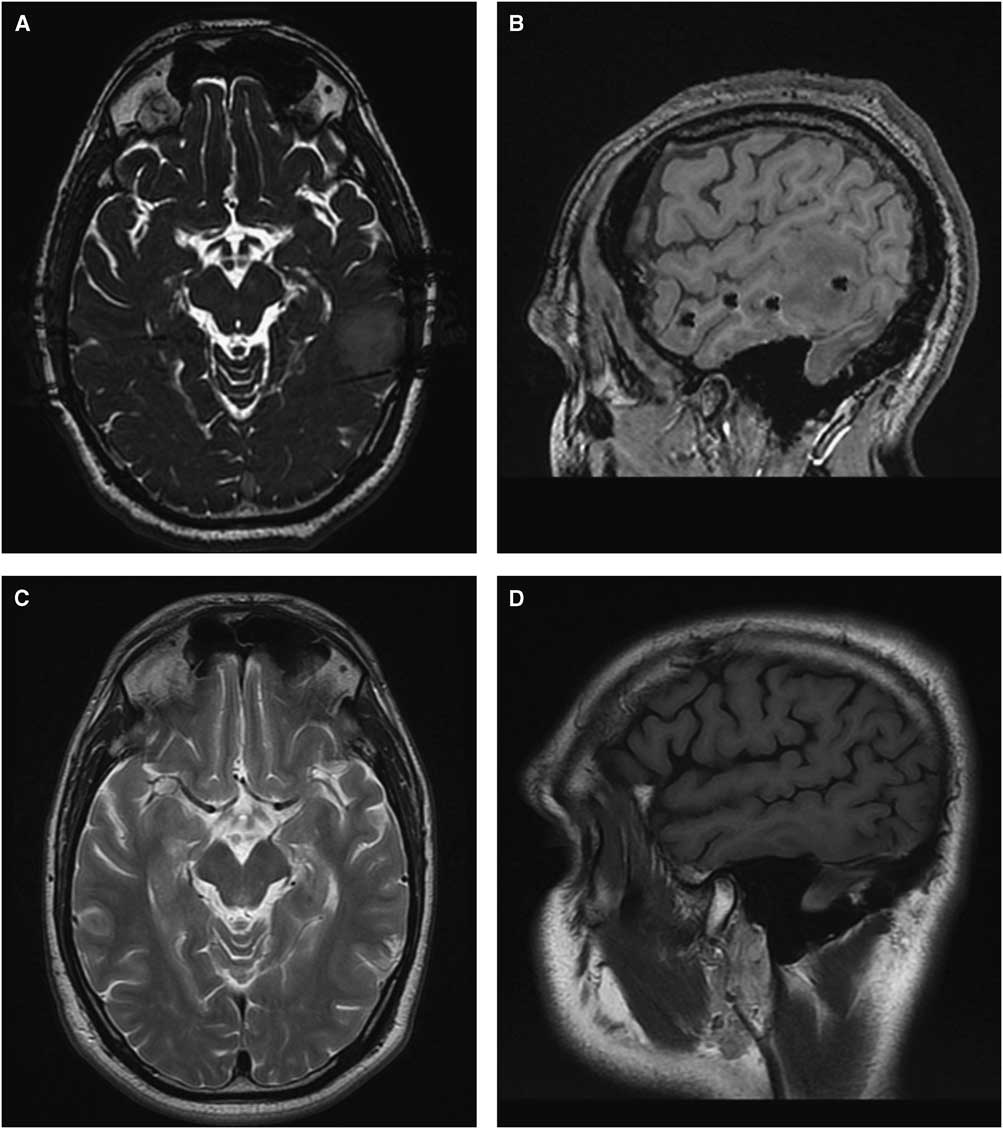

A careful review of each patient’s MRI with the electrodes in situ revealed four unexpected findings (three in the manual group and one in the robot-assisted group, p=0.287). Figure 2A demonstrates an area of contusion without hemorrhage that resulted from a penetration of the anchoring screw through bone that had been weakened by previous pin fixation with the manual technique. Figure 2B shows a hemorrhagic contusion that likely occurred from an unintended perforation of the dura and cortex at the time of craniostomy with the manual technique. Figure 2C shows a subdural hematoma that likely occurred from an unintended perforation of the dura and/or laceration of a cortical vessel at the time of craniostomy with the manual technique. Figures 3A and 3B show venous congestion in the left posterior temporal area, most likely secondary to venous compression or coagulation with the robot-assisted technique. Figures 3C and 3D demonstrate its resolution at 3 months post-explantation.

Figure 3 Patient 34. (A and C) T2 axial section. (B and D) T1 sagittal section. A and B show venous congestion in the left posterior temporal area most likely caused by compression or coagulation of a vein. C and D show these changes to be largely resolved at 3 months post-explantation.